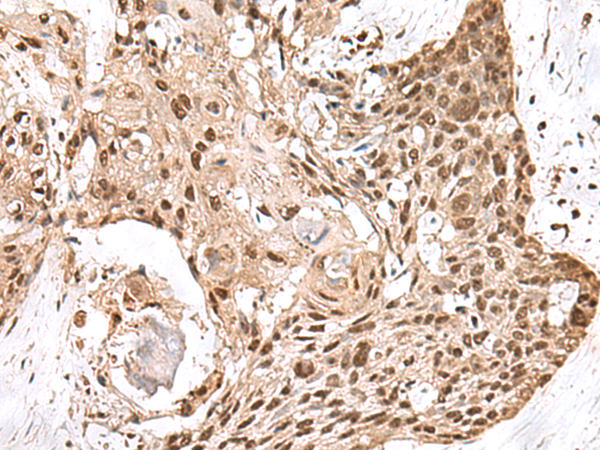

IHC positive control:

Human esophagus cancer and Human thyroid cancer

IHC Recommend dilution:

50-300